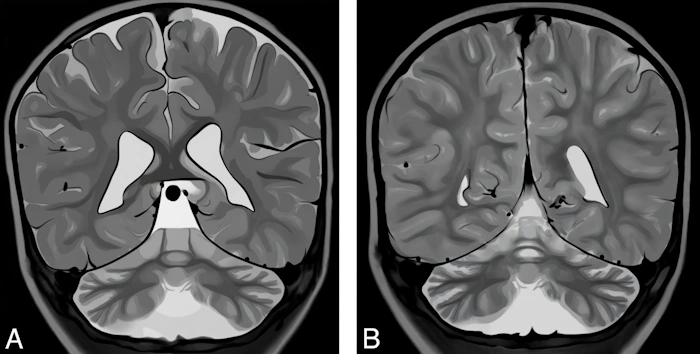

In Rett syndrome, the protein structure is disrupted, leading to its malfunction. Brain growth and development suffer, and the cerebral cortex and cerebellum atrophy (shrink) [11]. Thinning of the cerebral cortex leads to disruptions in speech centers and control of behavior and movement planning, while cerebellar atrophy causes coordination problems and tremor.

Digital illustration made based on the real image of the brain where atrophy of the cerebellum and cerebral cortex is shown. Image: re-cognition.center